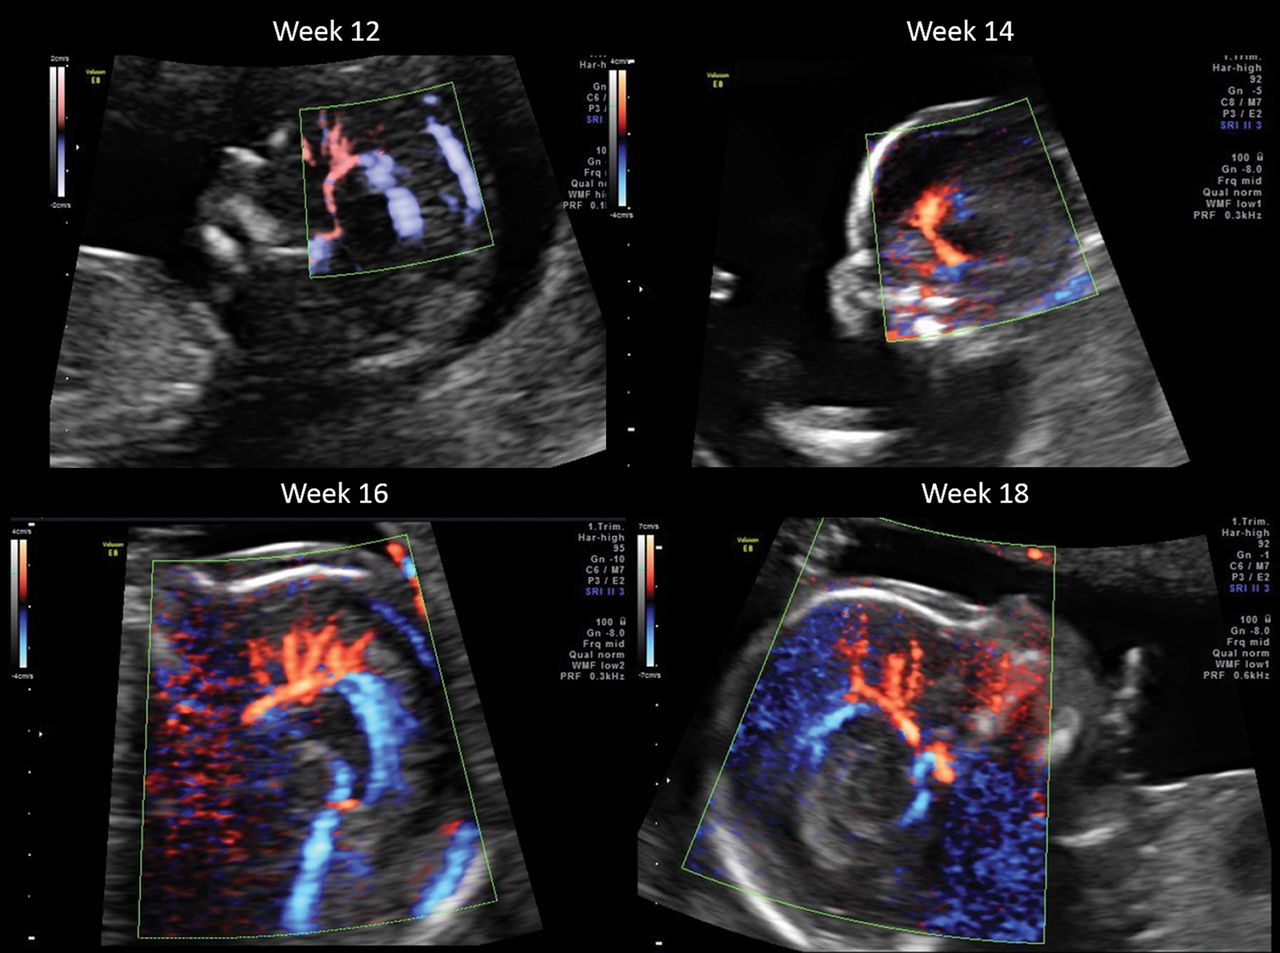

The different branches of the pericallosal arteries at week 12, week 14, week 16 and week 18, respectively.